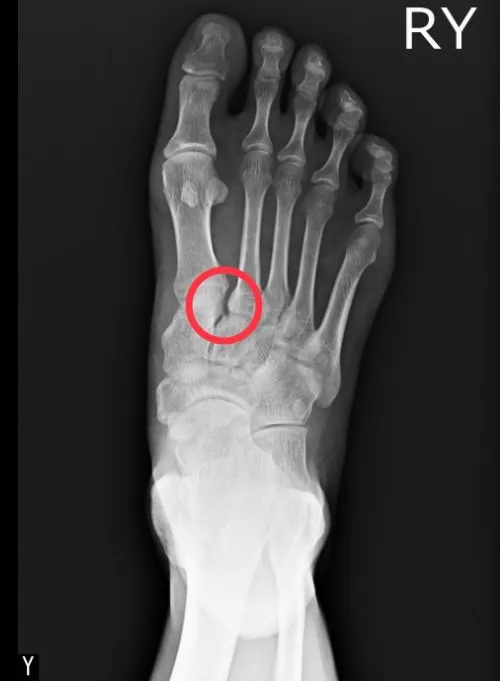

微創鋼釘固定手術治療後的X光照。大里仁愛醫院提供